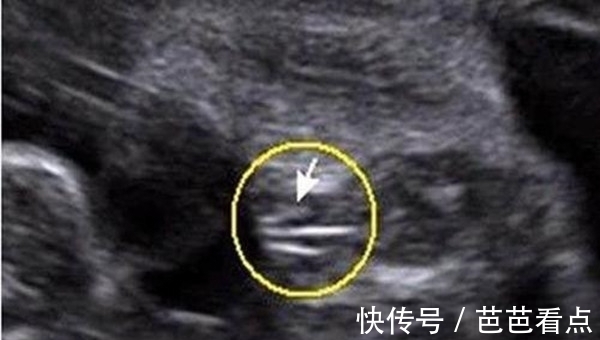

亮点一:看彩超图像

四维彩超单子,必须是照到胎儿宝宝的下半身,如果彩超图像有三条线的标志,那正是女孩的小阴唇,是非常明显的女性特征;如果彩超图像有突出的东东,像一团菌状的物体,那正是男性特有的标志。